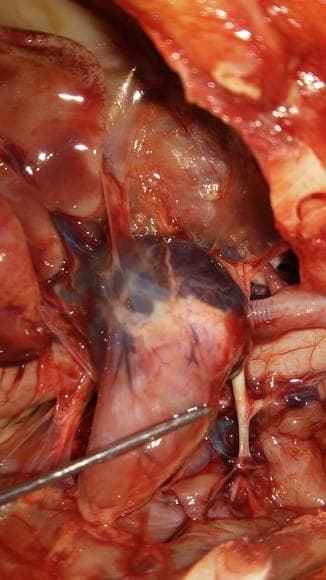

Vista do coração

Coração com sangue coagulado